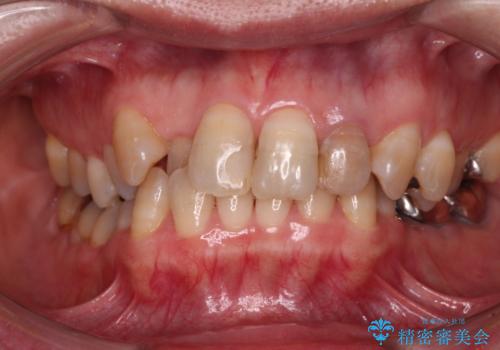

歯に独特の縞模様があり、さらに特徴的な色合いであったため、コンポジットレジンによる修復では対応が困難でした。

オールセラミッククラウンは周囲の歯よりもやや白く製作し手降りますが、今後はご自身でホワイトニングをして明るい色調で整えるとのことでした。